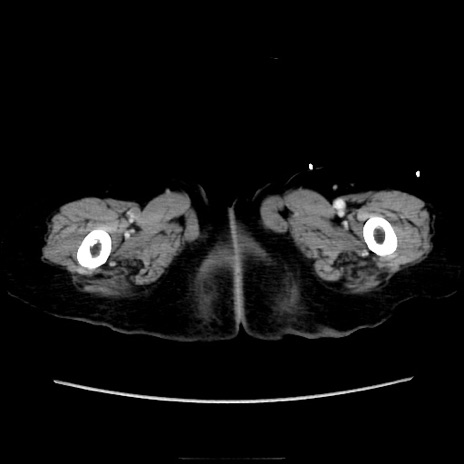

症例40(横断像)

【症例】90歳代女性

【主訴】腹痛・嘔吐

【現病歴】 食欲低下、嘔吐があり昨日他院受診。肺炎と診断され入院となる。入院後より腹部全体に圧痛あり。胃管留置され経過みていたが、症状持続するため、

当院転院となる。

【既往歴】胸椎圧迫骨折、胆石症

【身体所見】腹部:中央に激痛あり、圧痛あり、反跳痛不明

【データ】WBC 17100、CRP 18.82